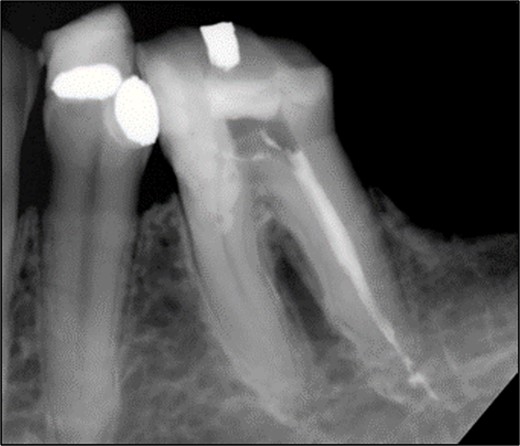

A 44-year-old patient presented to our clinic with the primary complaint of food lodgment in a cavity on the lower left posterior teeth. Clinical examination revealed extensive caries on the disto-occlusal surface of the lower left first permanent molar (tooth 36) (Fig. 1). Radiographic examination showed a large radiolucency at the distal crown extending to the cervical third of the distal root, with periapical radiolucencies on both mesial and distal roots (Fig. 2). The tooth was diagnosed with asymptomatic irreversible pulpitis and symptomatic apical periodontitis.

Periapical radiograph of tooth 36 showing a large radiolucency area at the distal crown involving the cervical third of the distal root.